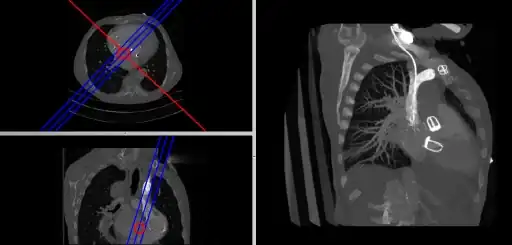

- Composite MPR Display

- Coronal and sagittal reconstructions are referred to as Orthogonal MPRs because the perspectives generated are from planes of image data which are at right angles to each other. Composite MPR displays can be generated so that linked cursors or crosshairs can be used to locate a point of interest from all three perspectives, as illustrated in Figure 5.19.

- Here the plane can be defined in, say, the axial images (red line, top left) and a maximum intensity projection (the limits used are highlighted by the blue lines), for example, can be displayed for the reconstructed plane (right). This technique is useful when attempting to generate perspectives in cases where the visualization of three-dimensional structures is complicated by overlapping anatomical detail.

- A final variant on the MPR theme is the generation of a three-dimensional display showing all three orthogonal projections combined so that a defined point of interest locates the intersection of the planes, as illustrated in Figure 5.22.

- The point of intersection is located for illustrative purposes at the centre of the voxel data in the figure. It can typically be placed at any point in the 3D data using interactive controls. In addition, the perspective used for the rotating sequence can be manipulated interactively to improve the visualization of a region of interest. Note that the image sequence illustrated is one from a myriad of perspectives that can thus be generated. Note also that slice projections (e.g. MIPs) can be combined with this form of display to provide additional perspectives on a feature of interest.